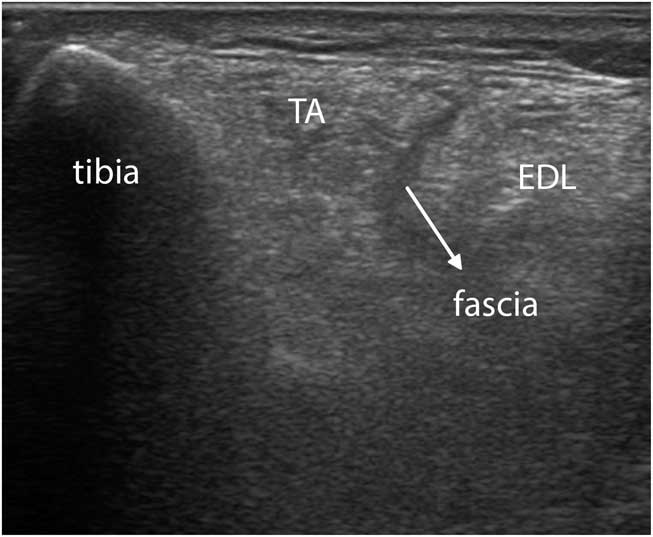

Figure 9 (A) Shows a transverse image of the ventral upper leg (VL), with the rectus femoris (RF) muscle lying in the middle on top, showing the typical oblique shape of its internal central fascia. (B) Shows a transverse image of the tibialis anterior (TA) muscle scanned at a 90° angle to obtain the brightest and best reproducible depiction of the underlying interosseus membrane and equal echogenicity of both muscle halves. EDL=extensor digitorum longus; VI=vastus intermedius; VM=vastus medialis.

To obtain the best reproducibility, the images should be made perpendicular to a reproducible structure such as bone or fascia underlying the muscle—for example, with the femur in the upper leg or the interosseus membrane in the lower leg (Figure 9B). This will ensure maximum reflection of ultrasound and hence the brightest image features on the screen.

Figure 11 Transverse image of a severely affected tibialis anterior (TA) muscle in facioscapulohumeral dystrophy. The intramuscular central tendon, as well as the intermuscular facia between the TA and extensor digitorum longus (EDL), now appear dark instead of bright (compare to Figure 9B). The interosseus membranes and deeper structures are no longer visible because of attenuation of the ultrasound caused by absorption and scattering of the beam.